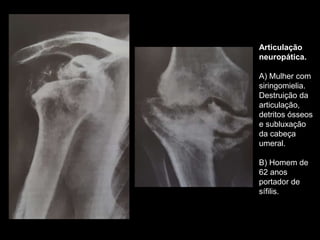

Articulação

neuropática.

A) Mulher com

siringomielia.

Destruição da

articulação,

detritos ósseos

e subluxação

da cabeça

umeral.

B) Homem de

62 anos

portador de

sífilis.